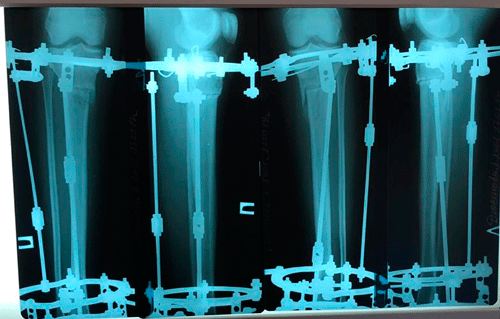

Исходник - 17 лет. Астана.

Ротация с обеих сторон.

Дата операции - 25.01.2019г.